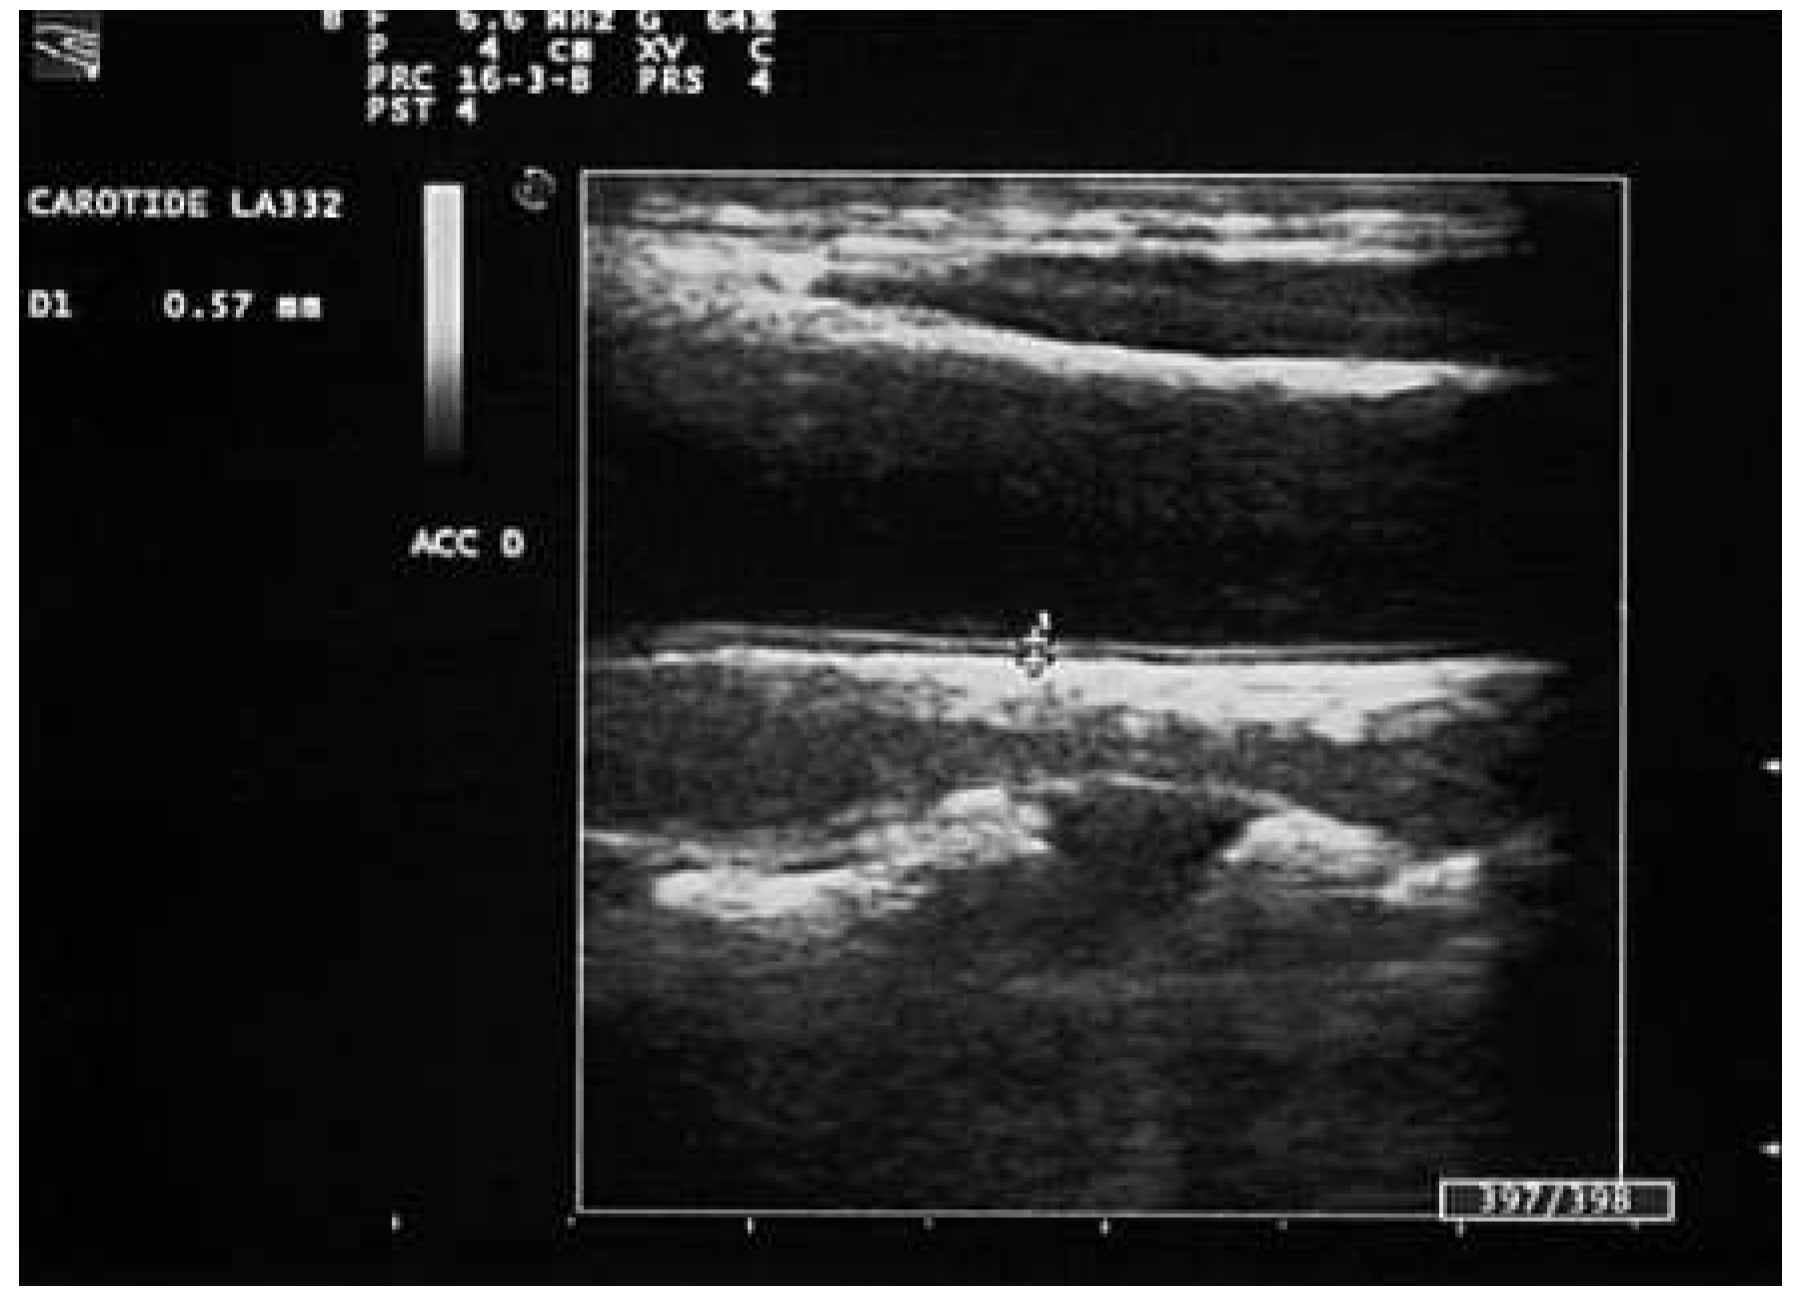

- Role of the carotid intima-media thickness